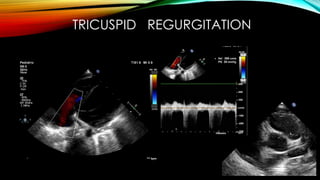

TRICUSPID REGURGITATION

Echo finding :perivascular brightnes Absence of tapperingin coronaries Decrease LV function Pericardial effusion Mitral regurgitation. Dilated aortic root. And Z score for left anterior or right coronary between 2-2.5 With early treatment, rapid recovery from the acute symptoms can be expected, and the risk of coronary artery aneurysms is greatly reduced. Untreated, the acute symptoms of Kawasaki disease are self-limited (i.e. the patient will recover eventually), but the risk of coronary artery involvement is much greater. Overall, about 2% of patients die from complications of coronary vasculitis Z score Interpretation <2 Normal 2-2.5 Mild dilatation or ectasia 2.5-5 Small coronary aneurysm 5-10 Medium > 10 Giant aneurysm RV RA LV